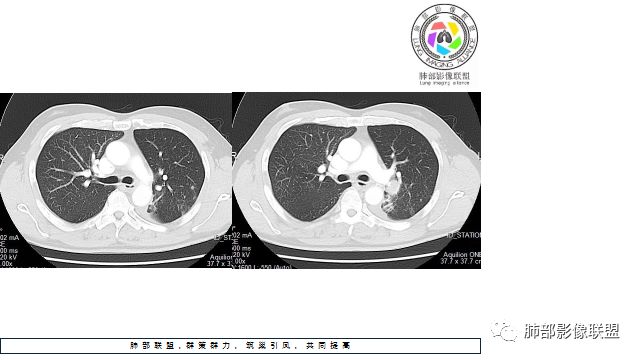

1.左下肺门区巨大肿块,支气管显示不清,轻度阻塞性炎症,没有明显肺不张,提示管腔受压狭窄可能性大于堵塞,这较少见于鳞癌。

4.病灶内有肺动脉走形,血管局部受压,未见破坏,病灶乏血供,呈血管包埋或血管造影征;侵袭性力强及破坏力弱、血管漂浮都符合SCLC,所以鳞癌的可能性也不大。

5.左肺门块影或淋巴结肿大,竭力挤兑肺门血管结构,呈冰冻肺门;有时候SCLC可以单独呈现冰冻肺门,而没有没有冰冻纵隔。

7.须特别注意的是,肺门区的融合块影,不排除它可能仅仅为转移淋巴结。